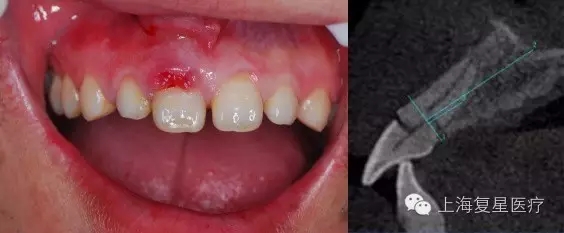

前牙即刻修復(fù)病例一例